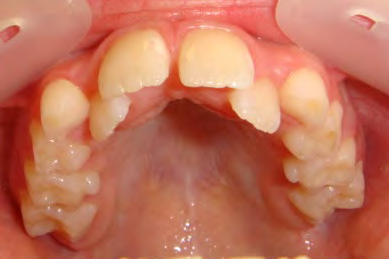

All of the patients below had been told they required extractions by orthodontists, some insisting that they could not be treated without extractions.

They were all treated without extractions, head gear or facemasks at Vakresmil and represent just a small sample of cases treated between 2004–2014.

The patient below had severe crowding of both upper canines and the lower right 5. The upper 4’s and 2’s were actually in contact.